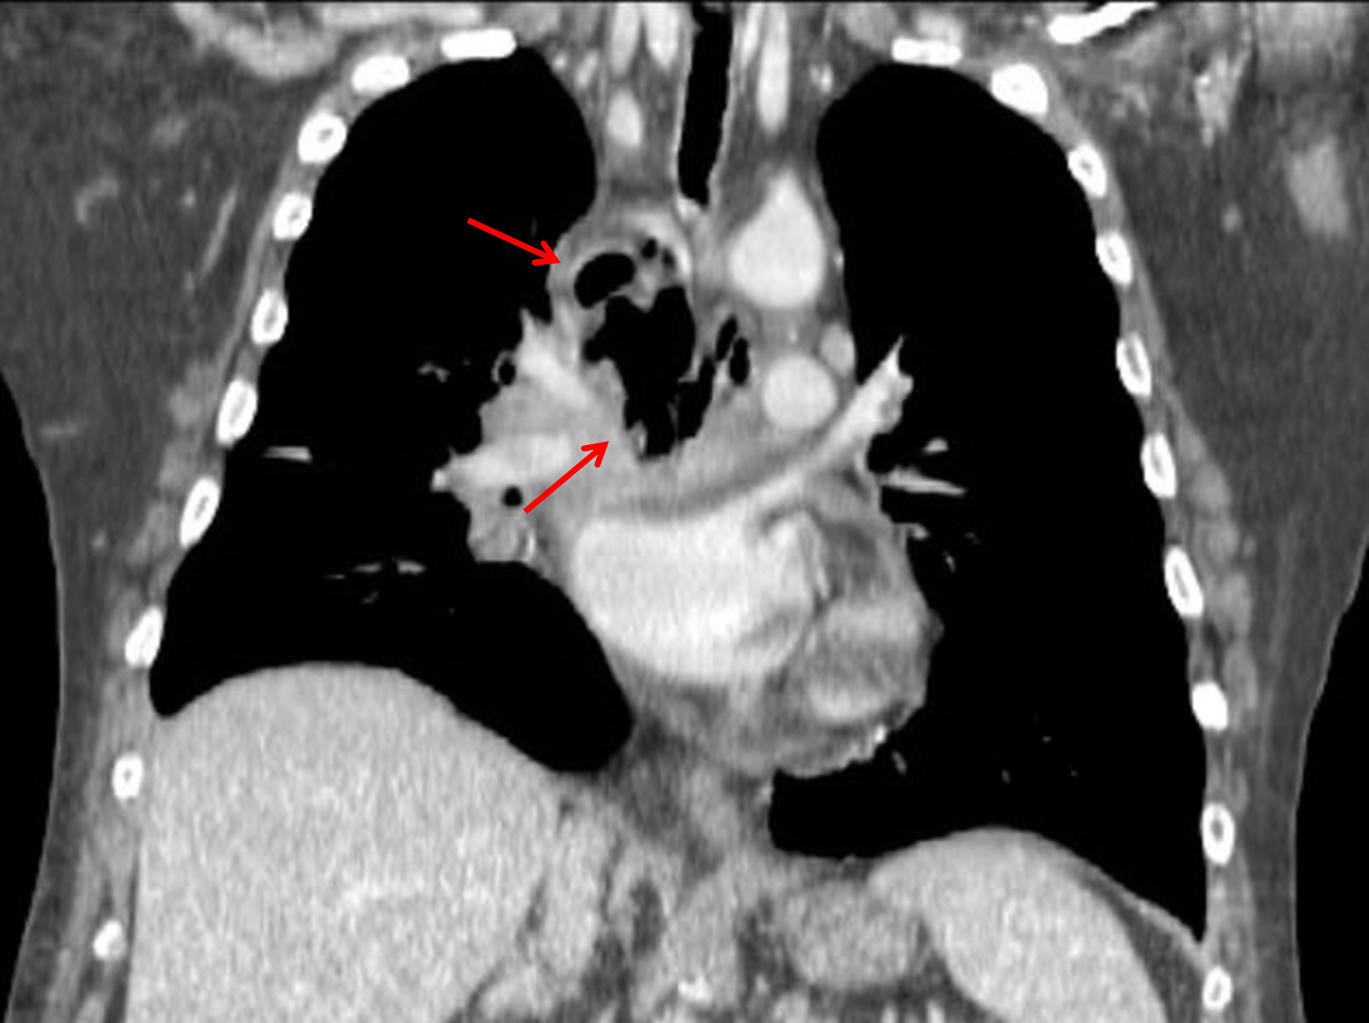

Age: 63

Sex: Male

Indication: Fever, dyspnea

Sample ReportWidening of the superior mediastinum with a rounded lucency along the right mediastinal margin, which findings raise particular concern for mediastinitis in the patient presenting with fever. Loculated mediastinal gas may relate to a necrotizing infection and/or communication with the trachea or esophagus. Recommend CT chest for further evaluation.

Patchy bibasilar airspace opacities are concerning for aspiration and/or pneumonia.

Small right pleural effusion.